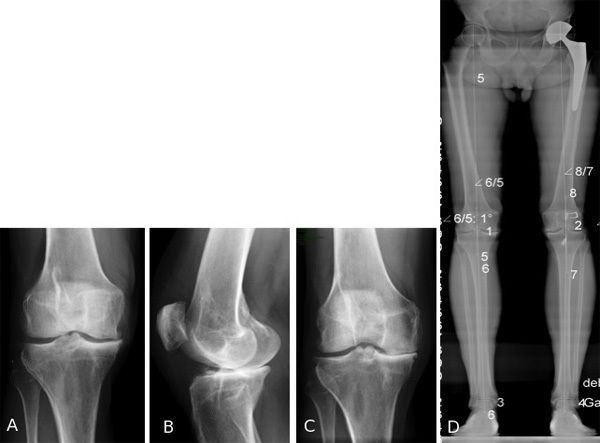

Patient de 57 ans opéré il y a 17 ans d'une reconstruction du ligament croisé antérieur associé à une méniscectomie médiale partielle. Gonarthrose fémoro-tibiale médiale modéré sur le cliché de face (A) et de profil (B) mais démasquée sur les clichés en schuss (C) sur un genou normo-axé (D).